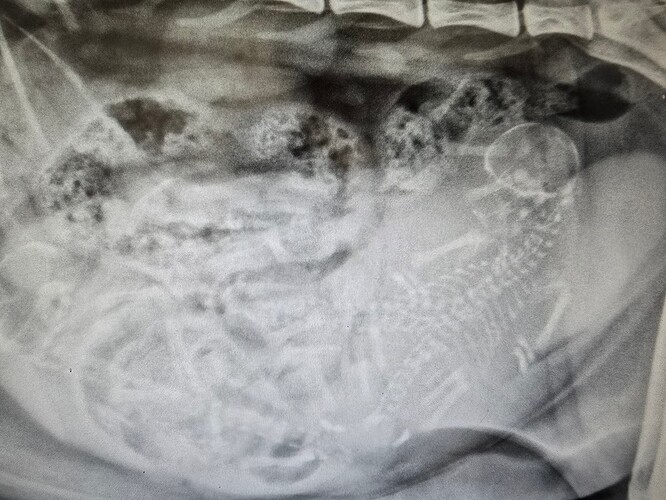

Så har vi været en tur forbi dyrlægen og fået taget røngten.

Hvor mange kan i tælle ??

Undskyld men jeg kan overhovedet ikke se nogle killinger -men jeg går ud fra, at de er der ? :wink:

Jeg er ikke ligefrem god til den slags billeder, men tror jeg ser 3-4 stykker.

Umiddelbart kun 3, men er slet ikke sikker :wink:

Jeg ser tre. Men jeg er jo som bekendt dårlig til det. :sweat_smile:

Jeps der er 3 styk og som _DK_Sugieh skriver, så kigger man efter rygsøjler og ser om der er samme antal hoveder, så er man sikker på at have talt rigtig.